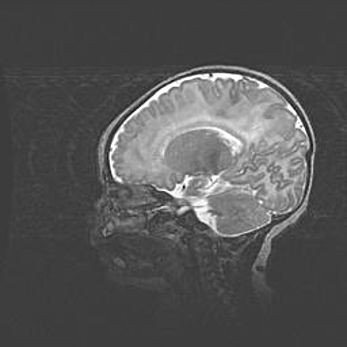

Мальформация Денди-Уокера. Киста задней черепной ямки.

Агенезия мозолистого тела.

Возраст: 2,5 месяца

Вес: 2420 г

Пол: женский

Окружность головы: 37 см

Срок гестации: 32 недели

Мальформация Денди—Уокера — редкий вид патологии ЦНС, представляющий собой врожденный порок развития каудального отдела ствола и червя мозжечка, ведущий к неполному раскрытию срединной (Мажанди) и латеральных (Лушка) апертур IV желудочка мозга. Для этогно синдрома характерна триада симптомов: гипотрофия червя мозжечка и/или полушарий мозжечка, кисты задней черепной ямки, гидроцефалия различной степени. В 70% случаев порок сочетается и с другими аномалиями головного мозга, в частности с агенезией мозолистого тела.